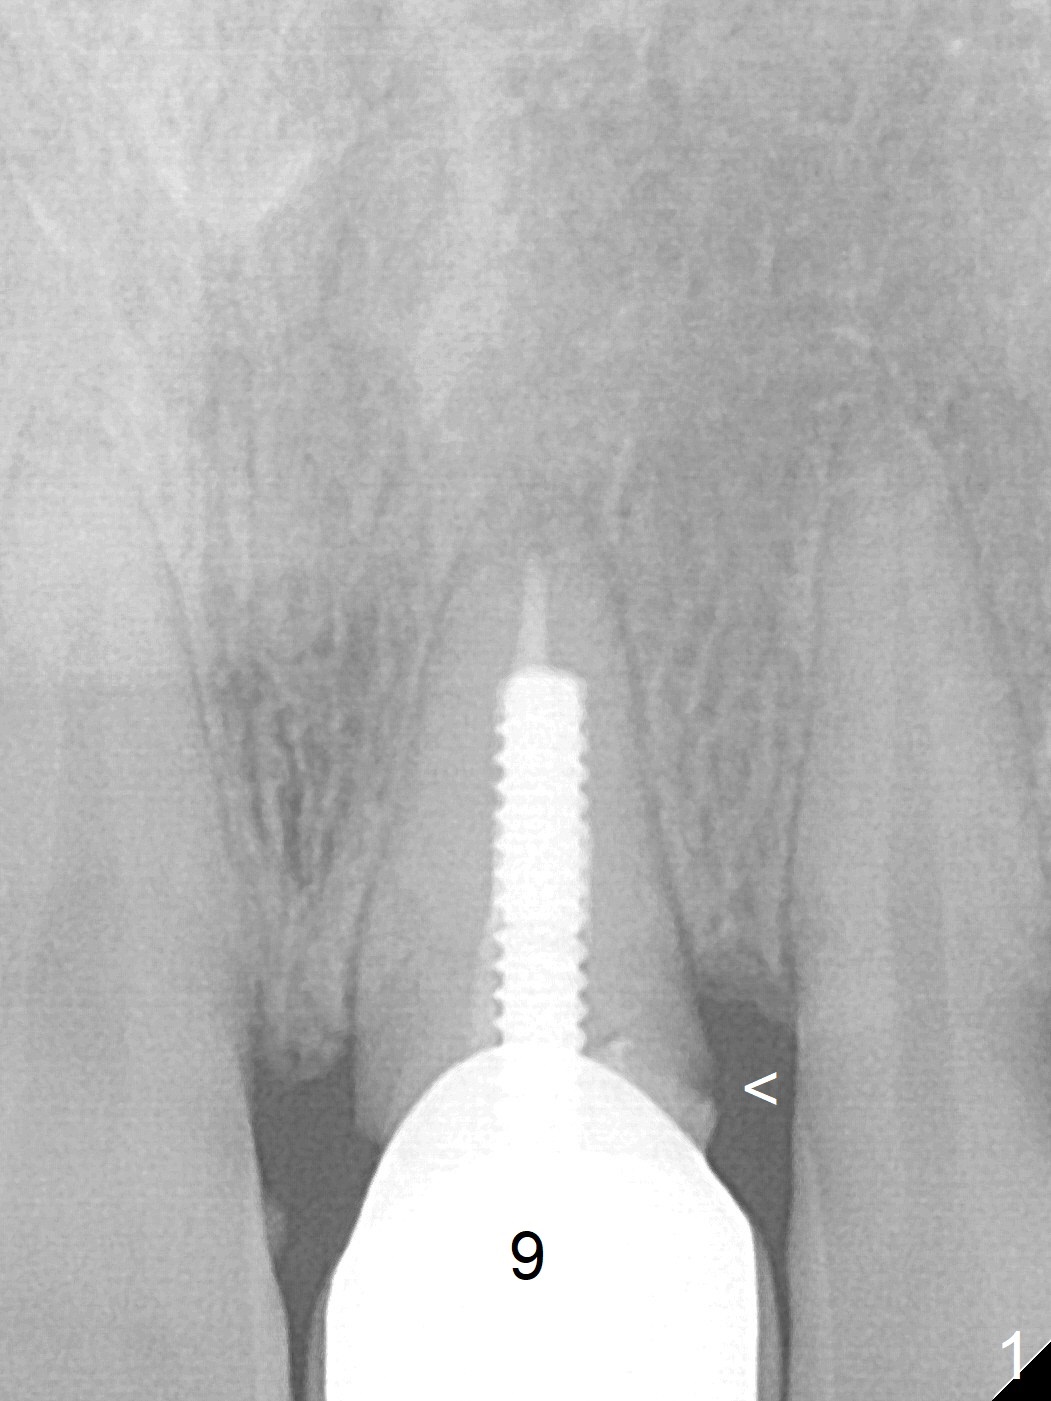

A 35-year-old woman's #9 fractures (Fig.1) because of blow by her child's head. Since a non-gold coated abutment will be used, an implant should be placed as palatal as possible (Fig.2). If the trajectory of the osteotomy turns out to be unacceptable, switch the other implant system with gold coated abutment. Perform socket shield, if extraction is difficult.